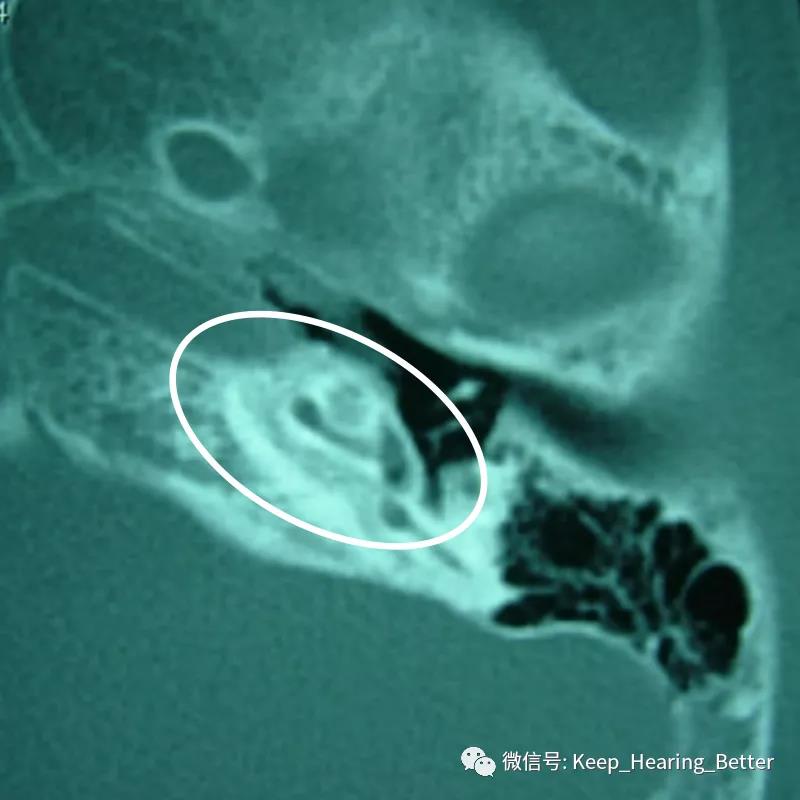

典型案例CT可见骨质疏松的双环征(如下图椭圆标记)、卵圆窗附近硬化灶(如下图箭头)等。